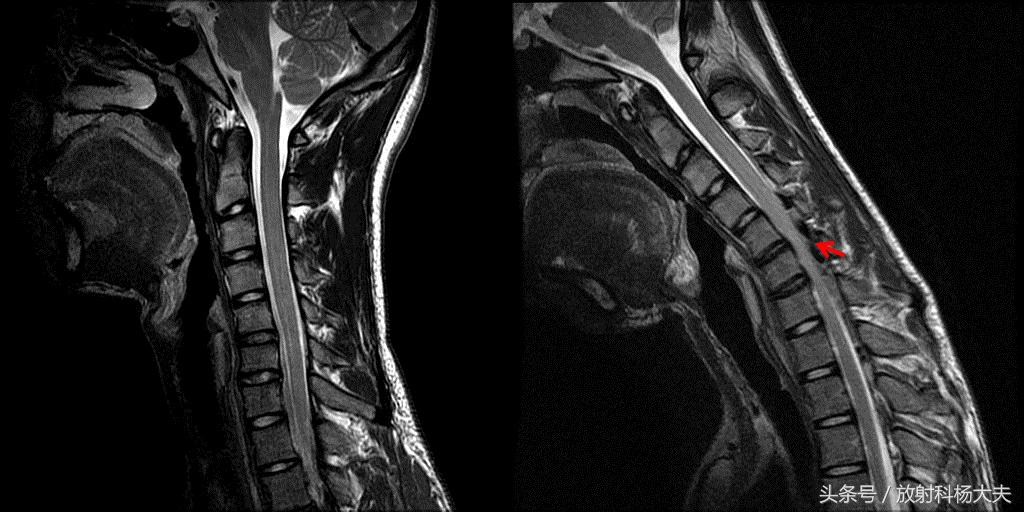

下图为病人的核磁矢状位,左侧为正常体位,右侧为过屈位,看起来没太多问题的颈椎在过屈位上原形毕露!

这是典型的平山病的表现!

平山病的典型MRI表现主要是自然位时颈椎曲度异常,表现为曲度变直或反弓,低位颈髓可以也可以不出现萎缩、变扁,但在过屈位低位颈髓的萎缩变扁会很明显,且在脊膜后间隙内在T1WI及T2WI出现 等、低混杂的新月形异常信号,其内可以看到流空的血管影。